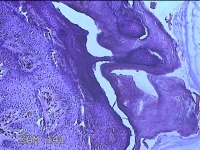

左侧臀部结节

性别

女

年龄

24岁

临床诊断

皮下结节

一般病史

发现左侧臀部结节1年余。

标本名称

大体所见

灰白暗红色带皮肤样结节0.7x0.3x0.2cm一个,表面糜烂,切开结节呈实性,切面灰白暗红色,质软。

图3